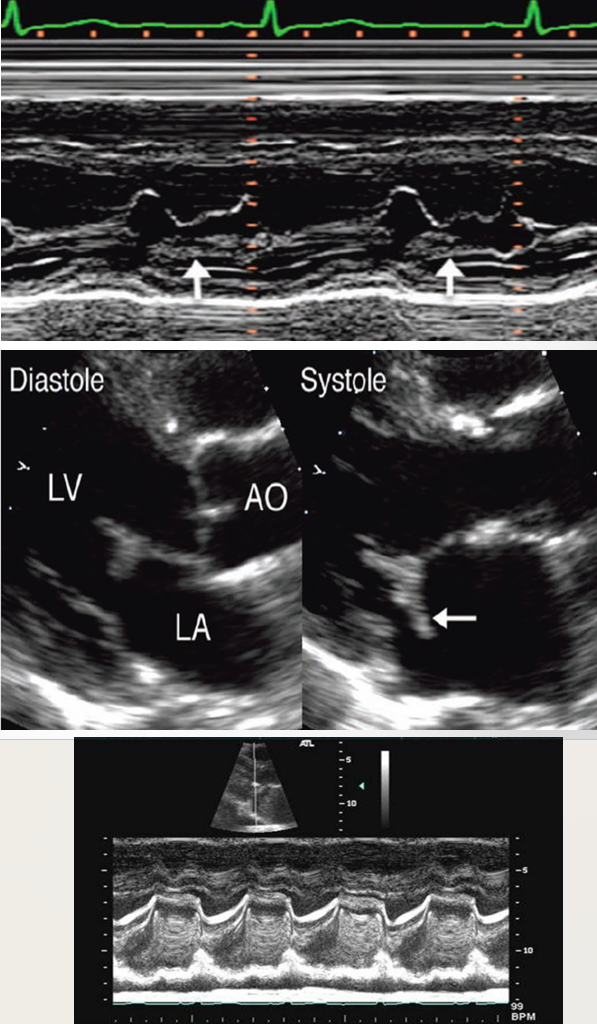

what is this?

abscess

what is seen here?

periannular absces adjacent to sewing ring